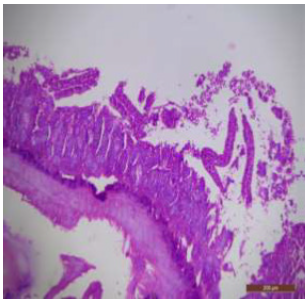

There was disruption in the villus architecture with crypt loss. The submucosa, muscularis externa and outer serosa were undifferentiated and were not clearly seen (Figure 6). There was marked villous atrophy, characterized by the shrinking and flattening of the intestinal villi. Additionally, mucosal erosion was also evident, indicating the wearing away of the protective mucosal layer (Figure 7). The duodenal tissues showed widespread disruption, with visible signs of structural disorganization and inflammation (Figure 8). The jejunum of control rat showed distinctive layers, i.e; mucosa, submucosa, muscularis and serosa (Figure 9). The jejunal mucosa was formed of epithelium, lamina propria and muscaris mucosa. The mucosa appeared as finger like projections with a core of connective tissue covered with enterocytes. Goblet cells were also seen in between the cells which are specialized type of epithelial cells, secrete mucus to neutralize the acids produced by stomach (Figures 10,11).

Figure 7: T.S. of duodenum of rat treated with 600 mg NaF/kg b.w./day for 40 days showing villous atrophy (↑) and mucosal erosion (↑). H&E × 40.

Figure 8: T.S. of duodenum of rat treated with 600 mg NaF/kg b.w./day for 40 days showing widespread disruption and structural disorganization. H&E × 40.

In fluoridated rats damaged and broken villi, focal intervillous haemorrhages and ulceration was present (Figure 12). There was shortening and flattening of some of the villi (Figure 13), distorted crypts, large swollen goblet cells lined by columnar epithelium with wide spaces were present (Figure 14). Distortion of different layers of mucosa with the loss of villous architecture and shedding of surface epithelium was seen in the jejunum of fluoridated rats (Figure 15). The villus architecture was notably disturbed, with a marked loss of crypts. Furthermore, there was a noticeable decrease in the number of goblet cells (Figure 16). The villi appeared scattered and fragmented, indicating a disruption in their typical architecture. Reduction in size of intestinal glands highlighted the detrimental impact of fluoride exposure on the intestinal morphology of rats (Figure 17).

The ileal mucosa of control rat was built up of numerous folds forming the villi, through which connective tissue of the lamina propria containing tubular glands i.e., crypts of Leiberkühn were present (Figure 18). The epithelial lining of the villi was composed of Paneth cells and intestinal glands (Figure 19). In fluorotic rats, there were abnormal shaped, damaged and broken villi with bulbous tips. Lymphatic dilation and haemorrhaged in lamina propria were also seen (Figure 20). In the ileal mucosa, prominent inflammation, distortion of crypts with shredded cells inside the crypts were visible (Figure 21). Swollen and necrotic crypts were present (Figure 22). The ileal tissue showed disruptions in the normal mucosal architecture with signs of villous atrophy and cell infiltration (Figure 23). Lymphatic infiltration was prominent and numerous enlarged lymph nodules appeared in lamina propria of villi. There were ill-defined cell boundaries, vacuolated cytoplasm and pyknotic nuclei (Figure 24).

Figure 13: T.S. of jejunum of rat treated with 600 mg NaF/kg b.w./day for 40 days showing distortion, shortening and flattening of villi (↑). H&E × 100.

Figure 15: T.S. of jejunum of rat treated with 600 mg NaF/ kg b.w./day for 40 days showing atrophy of villi and distortion of different layers and destruction of surface epithelium (↑). H&E × 100.

Figure 16: T.S. of jejunum of rat treated with 600 mg NaF/ kg b.w./day for 40 days showing disruption of villi (↑), reduction in number of goblet cells (↑) and crypt loss (↑). H&E × 100.

Figure 17: T.S. of ileum of control rat showing scattered and broken villi (↑) and decrease in size of intestinal glands (↑). H&E × 100.